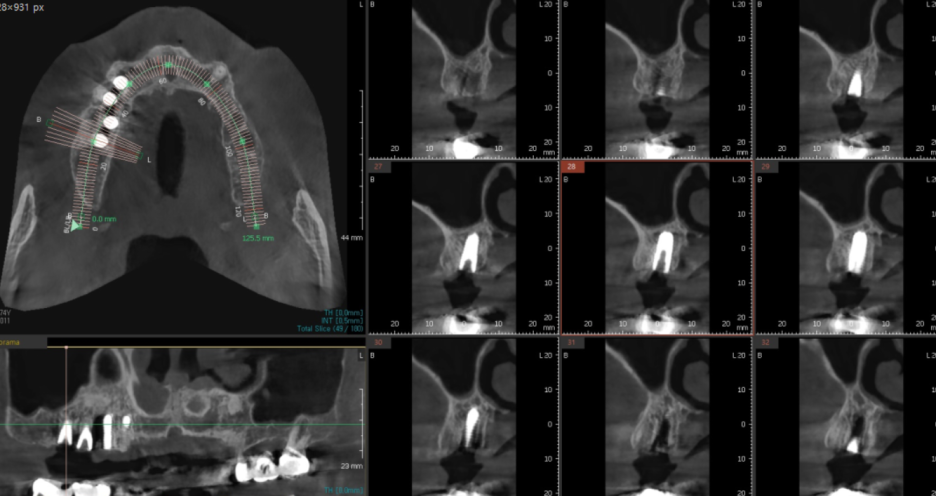

풍산동 치과에서 발치 후 임플란트 수술을

진행하셨습니다.

23.12.18

기존 금니 보철이 빠진 후

임플란트로 교체 해드렸습니다.

24.03.07